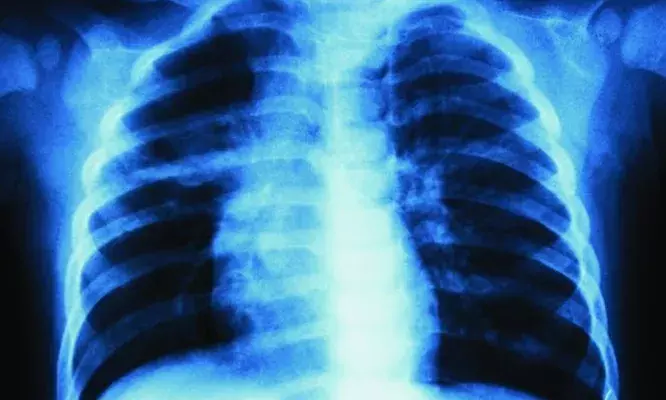

ബൈക്കില്‍ കാറിടിച്ച് പരിക്കേറ്റു; ഇടത് നെഞ്ചില്‍ വേദനയുണ്ടെന്ന് യുവാവ്; എക്‌സ്‌റെയെടുത്തത് വലത് ഭാഗത്ത്; കുഴപ്പമൊന്നുമില്ലെന്ന് ഡോക്ടര്‍; ആലപ്പുഴ മെഡിക്കല്‍ കോളജിലും ചികിത്സാപ്പിഴവ്

അമ്പലപ്പുഴ: ആലപ്പുഴ മെഡിക്കല്‍ കോളജിലും ചികിത്സാപ്പിഴവ് ഉണ്ടായതായി പരാതി. വാഹനാപകടത്തില്‍ പരിക്കേറ്റ് ആലപ്പുഴ മെഡിക്കല്‍ കോളജ് ആശുപത്രിയിലെത്തിച്ച യുവാവിന്റെ ഇടത് നെഞ്ചിന് പകരം വലതു നെഞ്ചിന്റെ എക്സ്റേ എടുത്തെന്നാണ് പരാതി. എക്‌സ്‌റേ പരിശോധിച്ച ഡോക്ടര്‍ കുഴപ്പമില്ലെന്ന് അറിയിക്കുകയും ചെയ്തു.

പായല്‍ക്കുളങ്ങരയില്‍ വെച്ച് ബൈക്കില്‍ കാറിടിച്ചാണ് യുവാവിന് പരിക്കേറ്റത്. നെഞ്ചിനും കാലിനും പരിക്കേറ്റ യുവാവിനെ നാട്ടുകാര്‍ മെഡിക്കല്‍ കോളജ് ആശുപത്രിയിലെത്തിച്ചു. ഇടത് നെഞ്ചില്‍ വേദനയുണ്ടെന്ന് അറിയിച്ചതിനെത്തുടര്‍ന്നാണ് ഡോക്ടര്‍ എക്സ്റേ എടുക്കാന്‍ നിര്‍ദേശിച്ചത്. എന്നാല്‍, എക്സ്റേ എടുത്തത് വലതു നെഞ്ചിന്റേതായിരുന്നു. പരിശോധനയില്‍ കുഴപ്പമൊന്നുമില്ലെന്ന് ഡോക്ടര്‍ അറിയിക്കുകയും ചെയ്ത് കയ്യൊഴിഞ്ഞു.

വേദന അസഹനീയമായതിനെത്തുടര്‍ന്ന് യുവാവിനെ തിരുവല്ലയിലെ സ്വകാര്യ ആശുപത്രിയിലേക്ക് മാറ്റി. ഇവിടെ നടത്തിയ പരിശോധനയിലാണ് എക്സ്റേ മാറിയ വിവരം തിരിച്ചറിഞ്ഞതും ഇടത് നെഞ്ചില്‍ നീര്‍ക്കെട്ടുള്ളതായി കണ്ടെത്തിയതും. കാലിന് ഗുരുതരമായി പരിക്കേറ്റ യുവാവിനെ പിന്നീട് അടിയന്തിര ശസ്ത്രക്രിയയ്ക്ക് വിധേയനാക്കി.